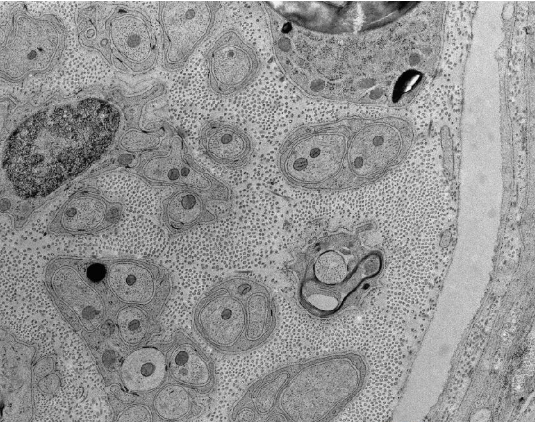

ultra45°4.0mm 适合,生物和材料科学标本的常规切片;

ultra Jumbo 45°4.0mm 适合, 3D重建系列,STEM